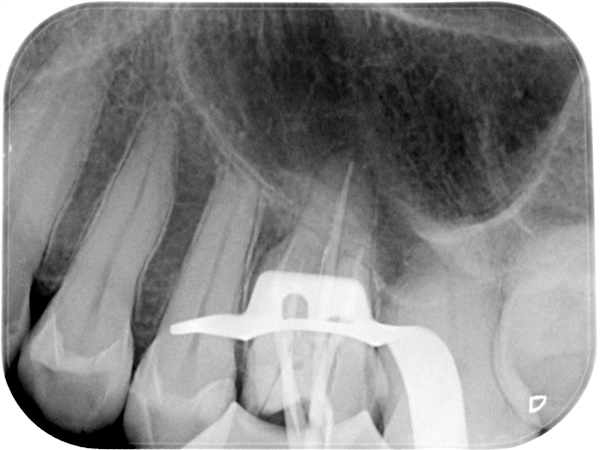

根管治療中(試適時)